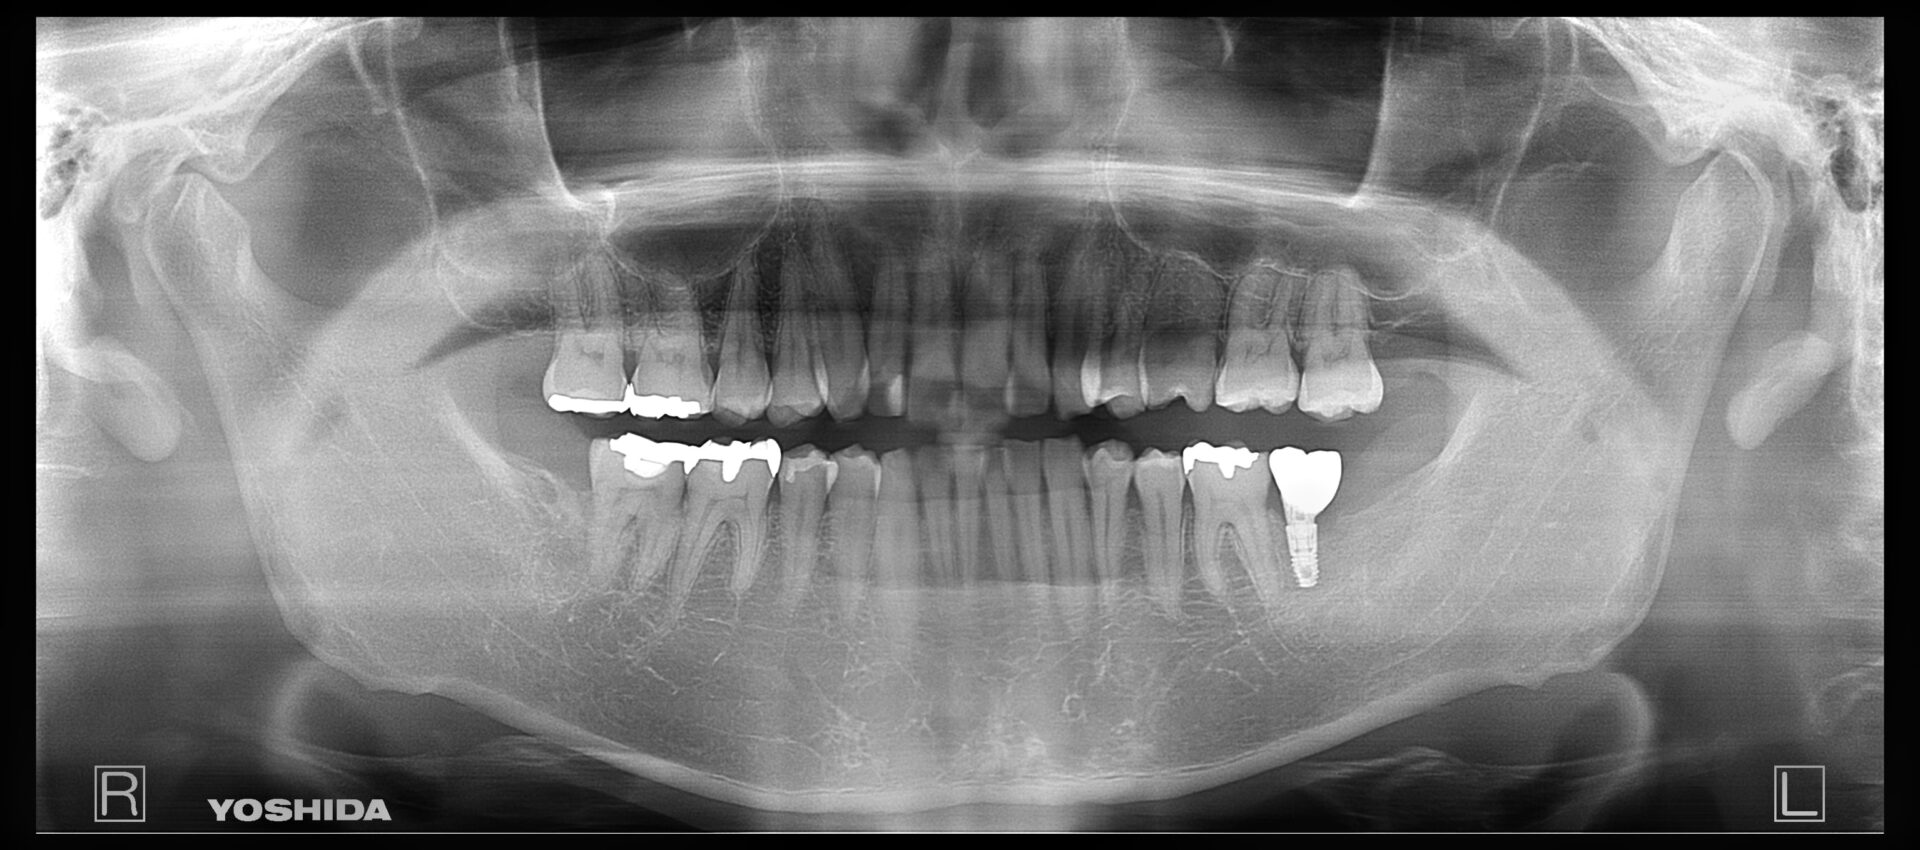

インプラント治療 右下奥歯 左上奥歯

歯の治療の開始前で右下と左上に歯がないところがあります。

治療を開始させていただく前のお口の中の状態です。

インプラント治療終了後3年の経過良好の状態です。

現在のお口の中の状態です。歯がないところに歯を回復させていただきました。

治療部位 | 右下76(インプラント+ジルコニア) |

費用 | (495,000円×4)約200万円 |

治療期間 | 6か月 |

下の奥歯がなく、食べにくいため、食べやすい治療方法を希望。

また、残っている歯に対する影響の少ない治療方法を希望され、インプラントを選択。